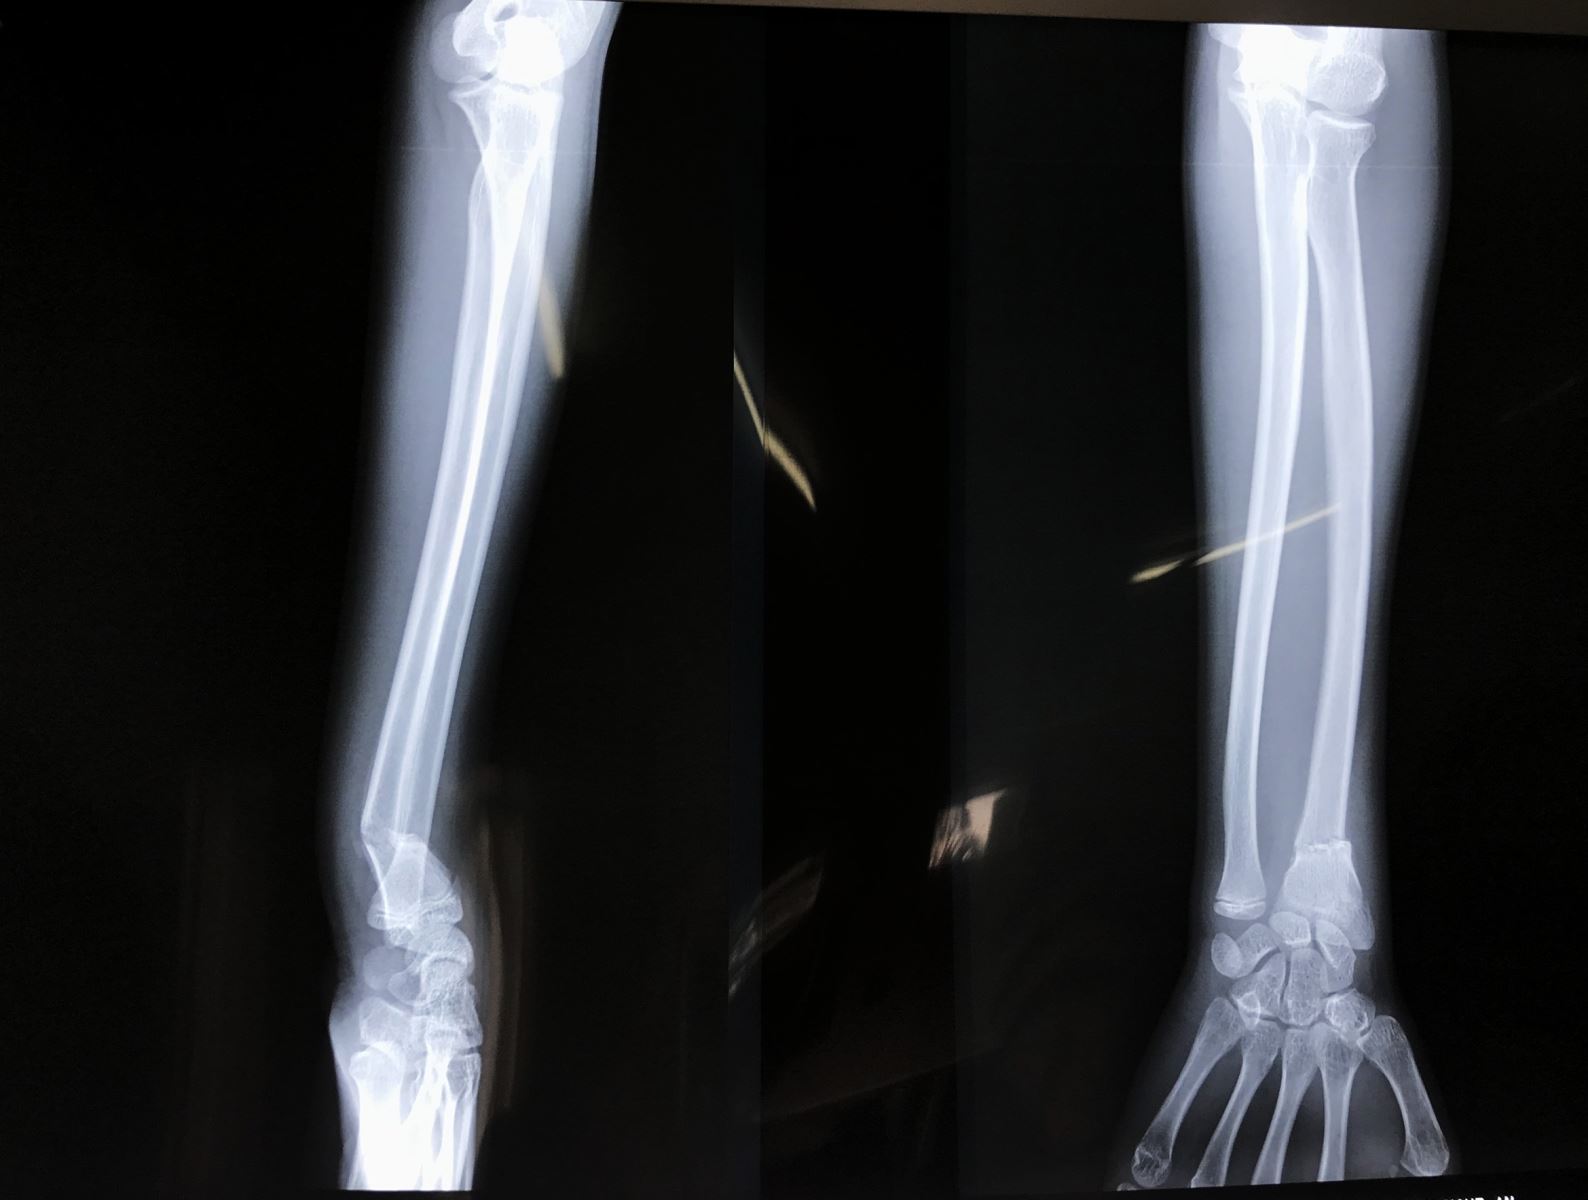

• X Quang cổ tay, cẳng tay thẳng nghiêng

X Quang khuỷu tay thẳng nghiêng nếu có đau về phía khuỷu hoặc có gãy thân xương